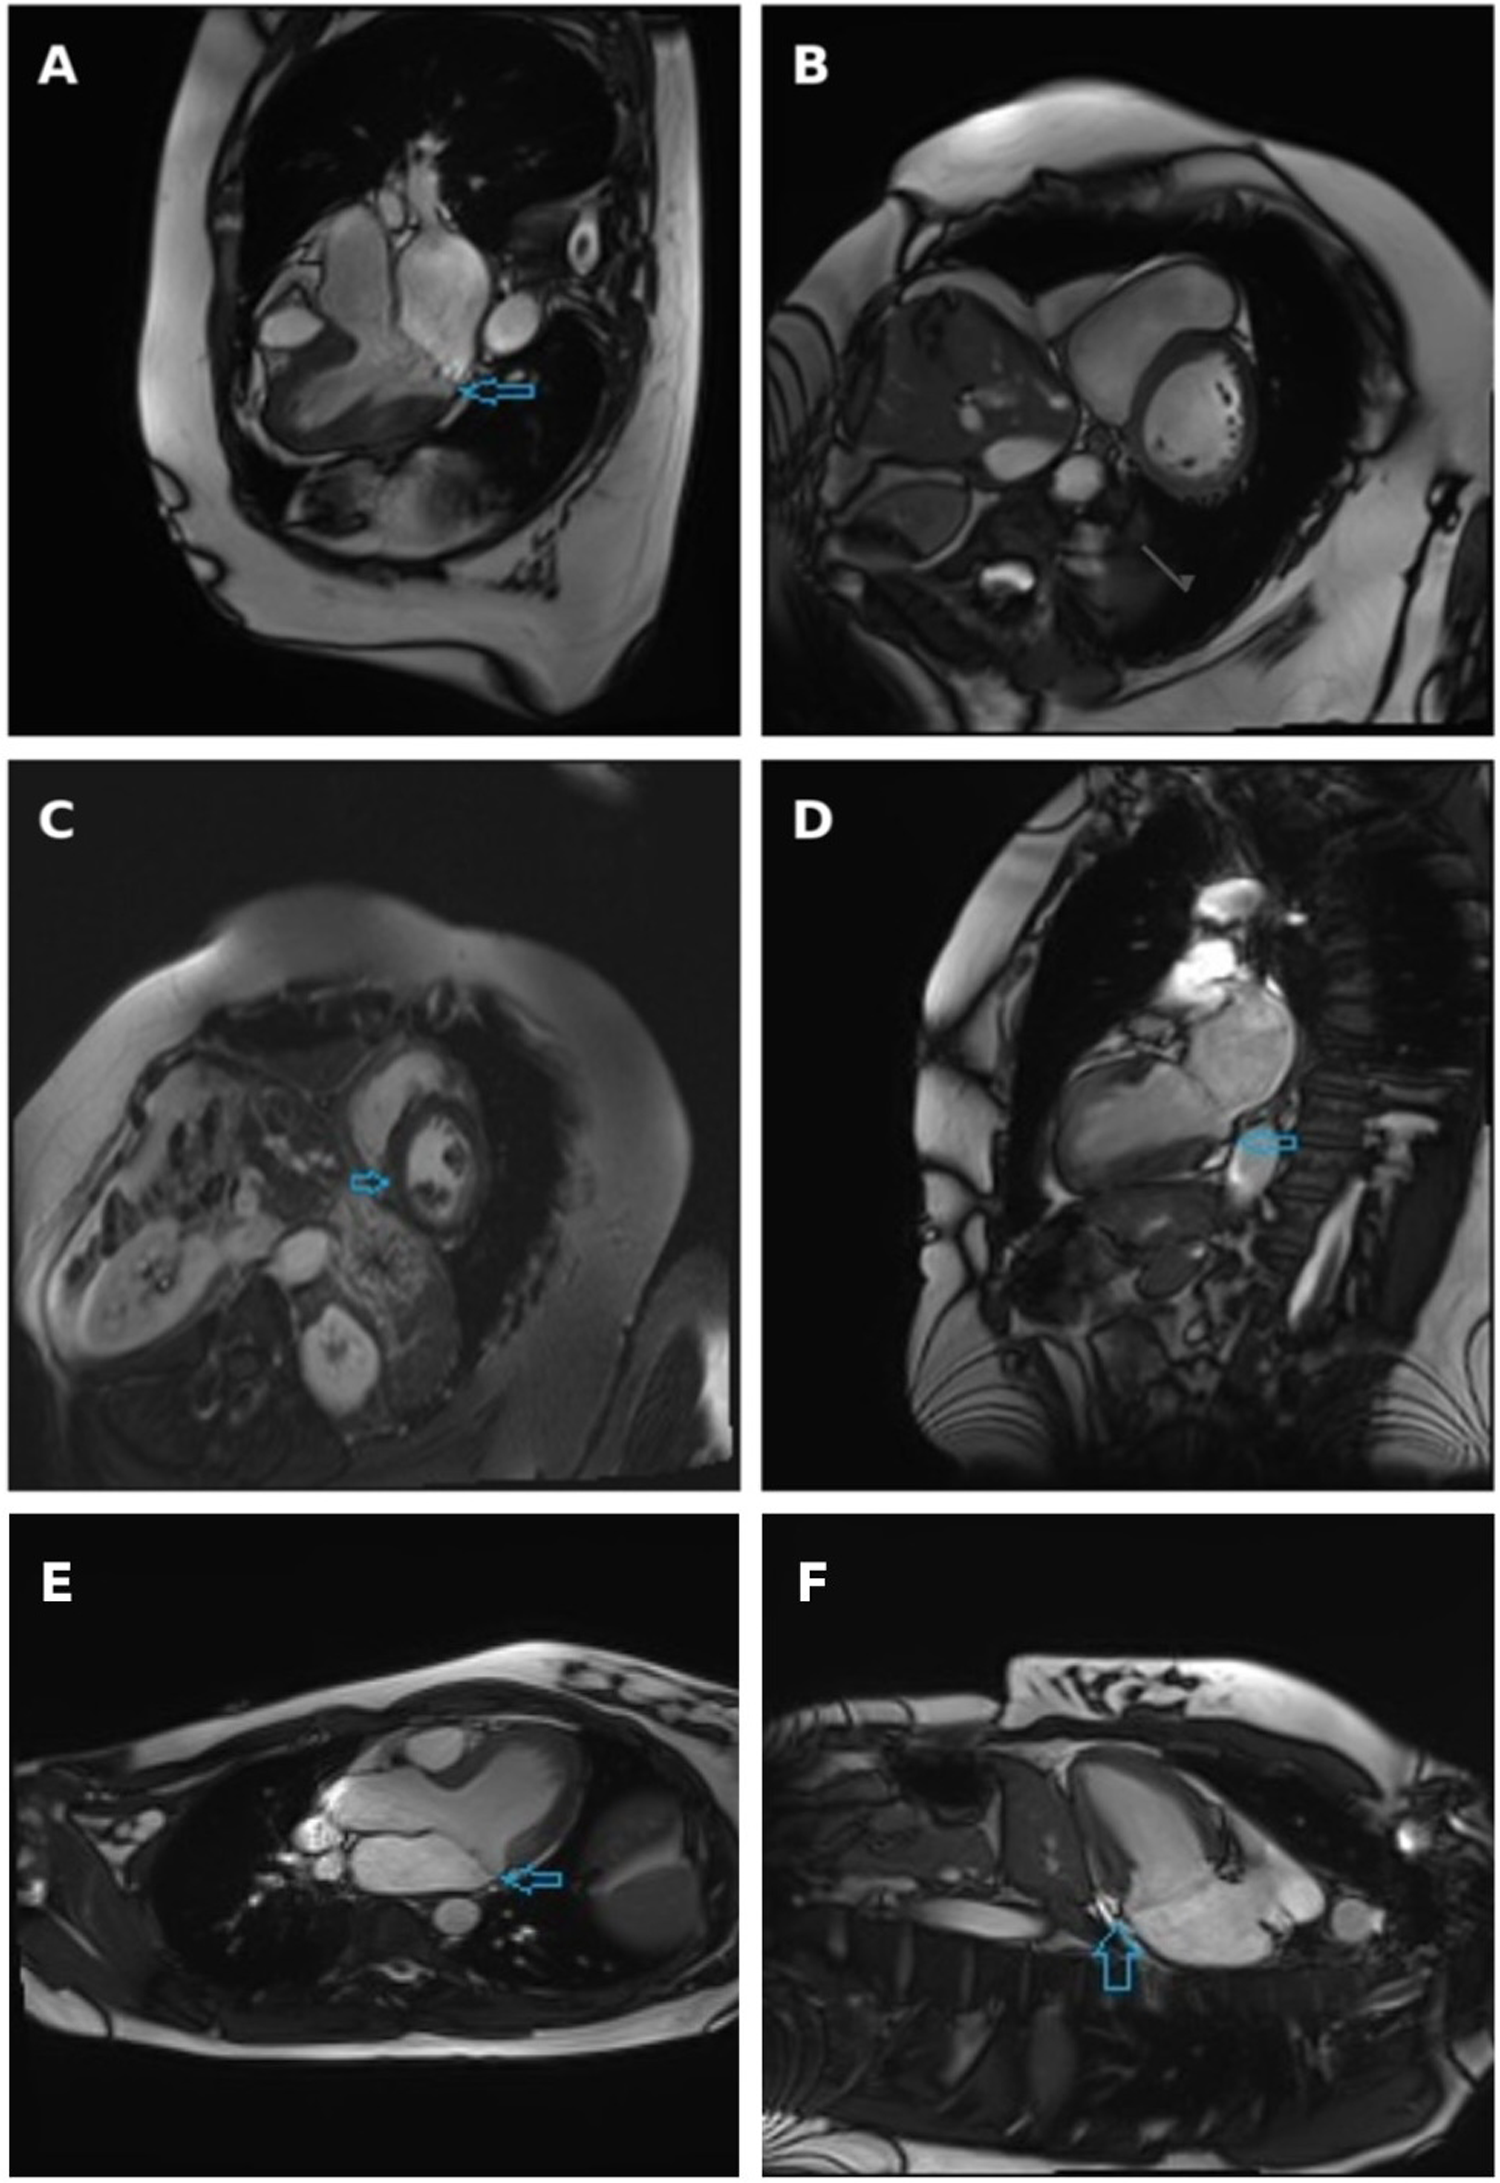

A comprehensive TTE revealed a thickened intraventricular septum, anterior MV leaflet prolapse, myxomatous degeneration of the MV leaflets, moderate to severe MVR with two eccentric jets, as well as LA and mitral annulus dilatation. Coronary artery angiography revealed mild non-obstructive coronary artery disease. CMR revealed inferior right ventricular insertion point fibrosis, moderate to severe MVR and MAD, all of which can be seen in Figure 2. Although LGE was detected, its distribution was located at the right ventricular insertion point, a site where enhancement is often considered non-specific and not necessarily indicative of a malignant arrhythmogenic substrate. Such findings, if isolated, should therefore be interpreted with caution, particularly in the absence of additional high-risk imaging features. However, additional Holter monitoring in this patient revealed polymorphic PVCs, several episodes of bigeminy, trigeminy and couplets. The PVCs exhibited both LBBB and right bundle branch block (RBBB) morphologies, suggesting multiple ectopic foci, most likely originating from the papillary muscles and/or adjacent inferior-basal LV myocardium. Moreover, a 12-lead ECG showed deep T-wave inversions in the inferior and lateral leads, which further supported the arrhythmogenic substrate and higher risk profile for this patient. The patient was discharged with a recommended adjustment of beta-blocker therapy and a plan for continued outpatient monitoring. A follow-up visit to a cardiologist was scheduled after 6 months, with 48 h HM and TTE assessment to be performed.

Figure 2

Cine three-chamber long-axis view (A), short-axis view at basal segments level (B) and two-chamber view (D) obtained at systole, with arrows indicating the separation between the posterior mitral valve leaflet insertion and the left ventricular myocardium. Late gadolinium enhancement short-axis view: arrow indicates non-specific fibrosis at the inferior right ventricular insertion point (C) Cardiac magnetic resonance imaging demonstrating mitral annular disjunction. Three-chamber long-axis view and (E) two-chamber view (F) obtained at end-systole, with arrows indicating the separation between the posterior mitral valve leaflet insertion point and the left ventricular myocardium.

MAD is best visualized in the TTE PLAX view and is often accompanied by myxomatous damage of MV leaflets. However, the most reliable and accurate tool used for the evaluation of fibrosis of myocardium and detection of MAD is CMR, as demonstrated in Figure 2. In a systematic literature review conducted by Drescher and colleagues, the diagnostic sensitivity of TTE and CMR was compared in the detection of MAD. MAD was detected in 17.3% of individuals using TTE, whereas the prevalence of MAD increased to 42.0% when the same individuals were assessed using CMR (13). To fully assess the extent of MAD, six LV long-axis cine sequences with 30° interslice rotation must be acquired around the mitral annulus, evaluating its' circumferential extent and maximal width of the disjunction (14). Another advantage of CMR compared to TTE is the ability to evaluate focal fibrosis of myocardium using LGE as well as diffuse LV fibrosis, which is associated with an increased risk of VAs, determined by T1 mapping (15). In presence of MAD, fibrosis is usually located close to the mitral annulus in the basal LV wall, including papillary muscles and inferior LV wall. Another common finding in patients with MAD is tricuspid annular disjunction (TAD), which, according to a study by Aabel et al., has been reported to occur in approximately 50% of examined MAD cases. The coexistence of TAD and MAD suggests a broader involvement of the atrioventricular junction rather than an isolated MV pathology and has been associated with a greater increase in the arrhythmic risk. Although standard CMR protocols can visualize the tricuspid annulus, TAD still often remains underdiagnosed (16). However, in the two cases presented in this study, no evidence of concomitant TAD was found on CMR.